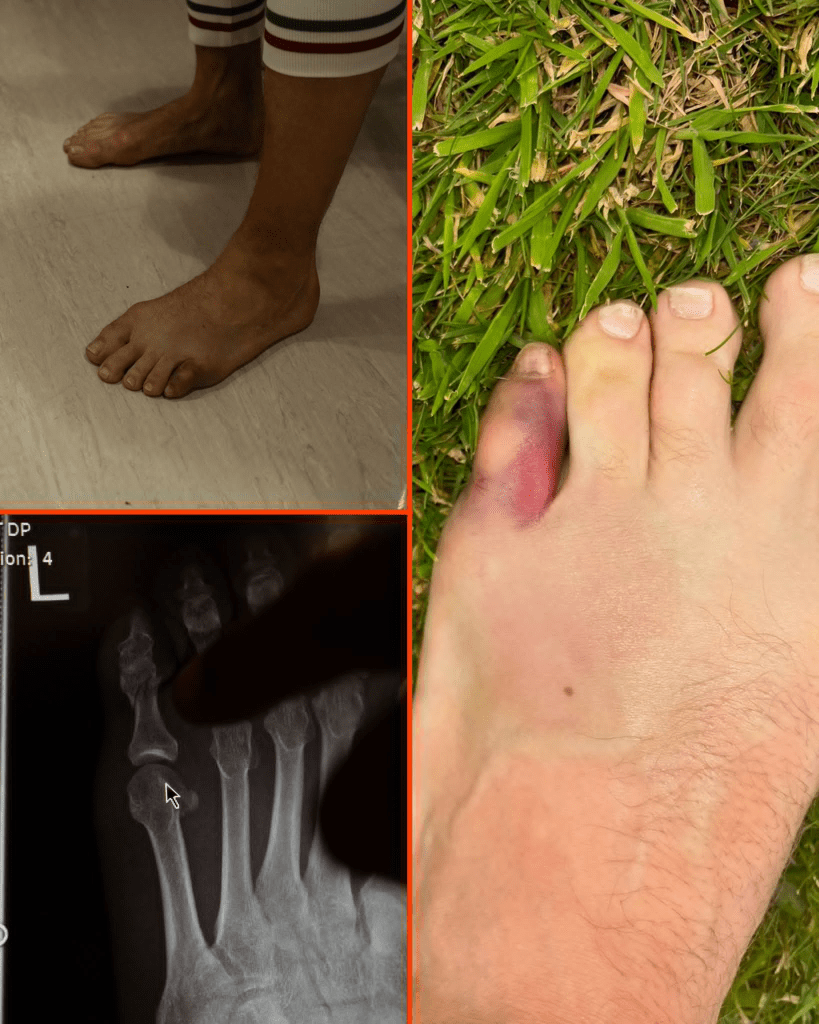

Conor McGregor antrenman esnasında serçe parmağını kırdığını açıkladı.

“Chael, kapa çeneni. Sen ground and poundda pes ettin.” diyerek kırık serçe parmağını ve röntgen fotoğrafını yayınladı.